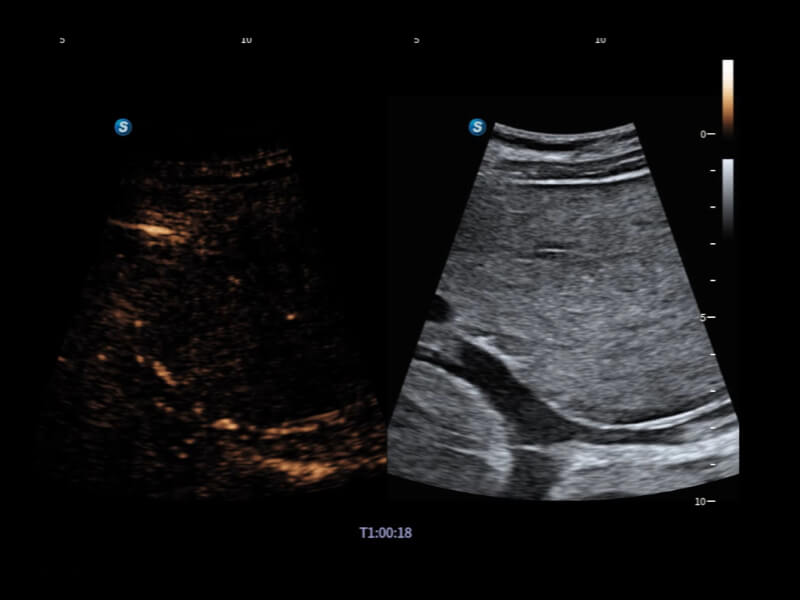

丰富的血流动力学检测技术,可在不同医疗场景中高效捕捉血流信号,助力临床诊疗。

在传统血流的基础上优化扫查和算法策略,能够更好的抑制组织信息,提炼红细胞运动信息,得到更高帧频,高灵敏度和分辨率的血流信号,还原更真实的血流动力学。

通过光照模型,使二维血流显示出立体的效果,增加血流的敏感性、成束性,减少外溢。可以和其他不同的血流技术联合使用,融合不同技术的优势。轻松应对微小血管,增强血流的立体效果,提升视觉敏感性。

通过创新的Matrix E自适应滤波算法,能有效滤除软组织和噪声信号,最大限度保留超低速微细血流的信号;结合超长时间域算法,极大提升细微血流的敏感性和空间分辨率,更真实的反应组织、包块的血流灌注情况。